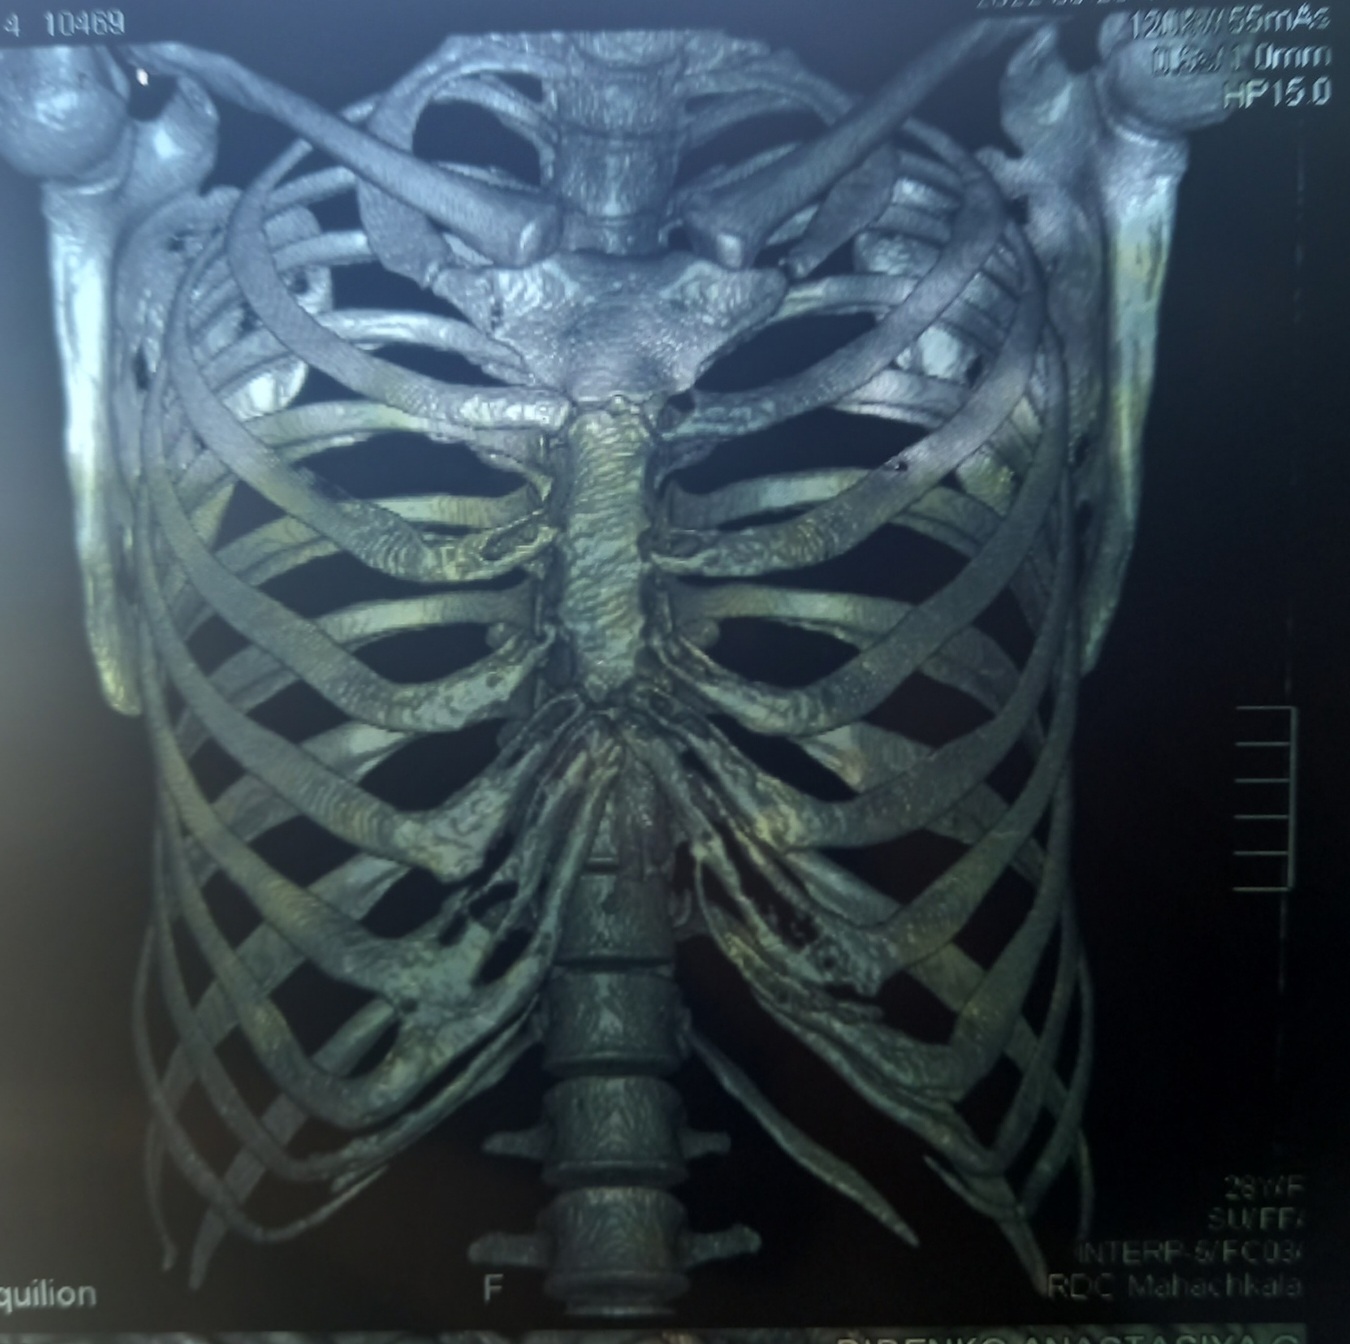

Медицина и диагностика: Аномалии ребер на рентгене